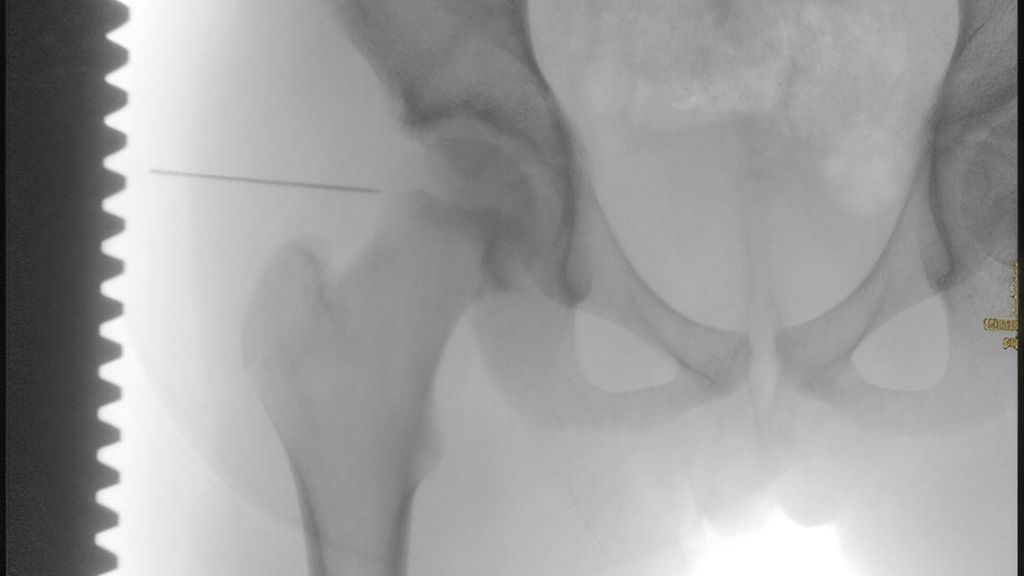

Abb. 1 a–c:11-jährige Patientin vorstellig mit diskret erhöhtem CRP von 0,8mg/dl ohne Fieber und Schonhinken der rechten Hüfte. Die Ultraschalluntersuchung zeigte einen Erguss, woraufhin eine Punktion des Hüftgelenks durchgeführt wurde (a). Bei klarem Erguss wurde von einer offenen Lavage initial abgesehen. Eine Keimdetektion aus gewonnenem Punktat war negativ. Im stationären Verlauf wurde aus der Blutkultur S. aureus nachgewiesen. Des Weiteren kam es zu einem Stagnieren der klinischen Besserung und einem Anstieg des CRP unter Antibiose. Eine MRT-Untersuchung zeigte einen Gelenkserguss mit begleitender Signalalteration im Sinne einer möglichen Osteomyelitis im ventralen Acetabulumbereich (b–c). Aufgrund dessen waren die offene Lavage und das Gelenks-Debridement indiziert

Die Etablierung eines Algorithmus wie in Abb. 2 ist hilfreich, um nach durchgeführter Diagnostik die adäquate Behandlung einzuleiten. Im Falle des Vorhandenseins positiver Infektionskriterien mit begleitendem Erguss des Hüftgelenks wird die sterile Punktion unter Ultraschall- oder Röntgenkontrolle empfohlen.32 Aus dem gewonnenen Punktat sollten mikrobiologische Untersuchungen wie eine Bakterienkultur, gegebenenfalls Gram-Färbung, PCR sowie Bestimmung der Zellzahl mit Differenzialzählung durchgeführt werden. Leukozyten-Grenzwerte von >50000 Zellen/mm3 und >75% segmentkernigen Granulozyten korrelieren mit dem Vorhandensein einer SA.33,34